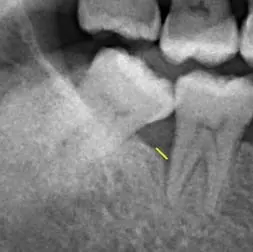

(治療半年後)

治療後X光片顯示說明:齒槽骨已長回80%,復原狀況良好齒槽骨內的骨頭逐漸生長,骨頭高度比治療前高出甚多。